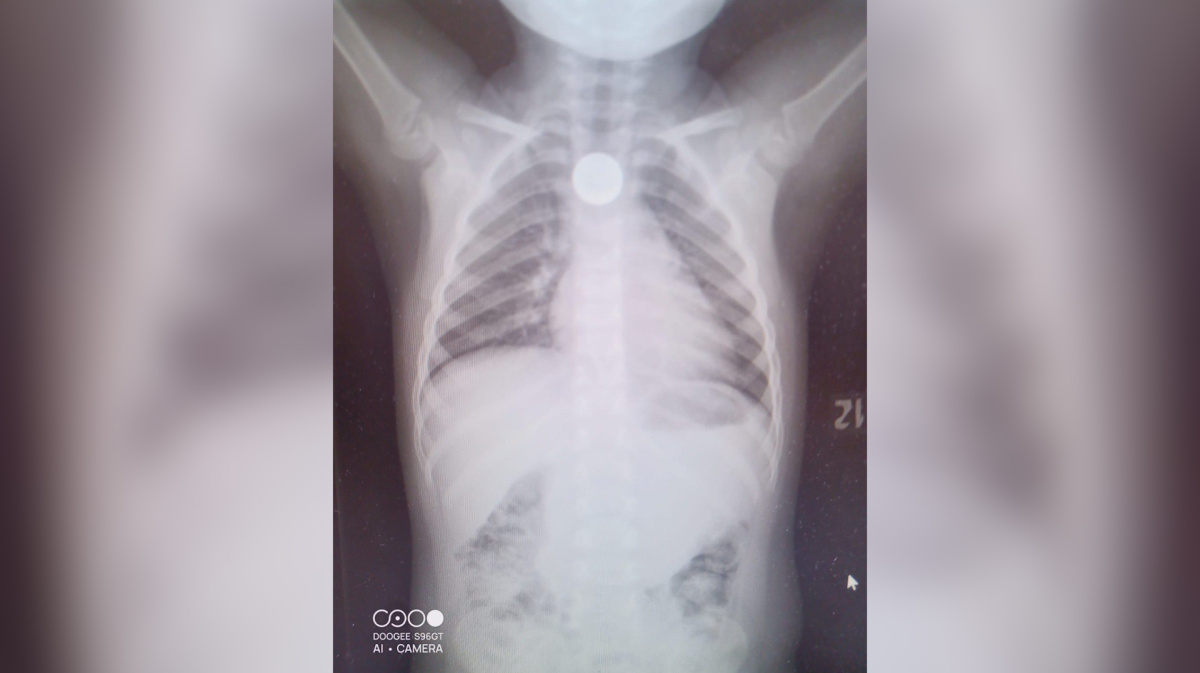

Ребенок проглотил камушек

Ребенок проглотил камушек 108 фото